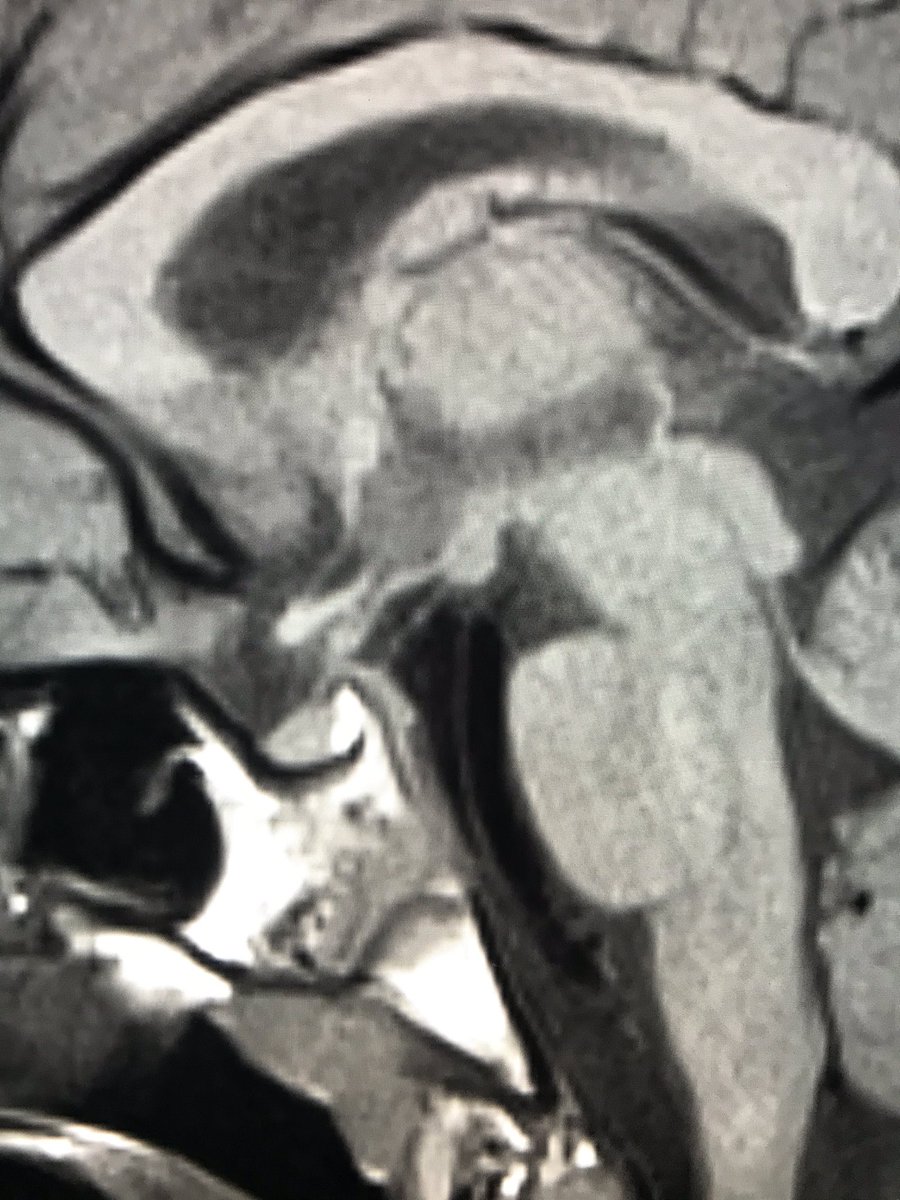

@The_ASPNR#radres#neuroradped when neuroanatomy comes out incidentally on a standard sellar MRI ..